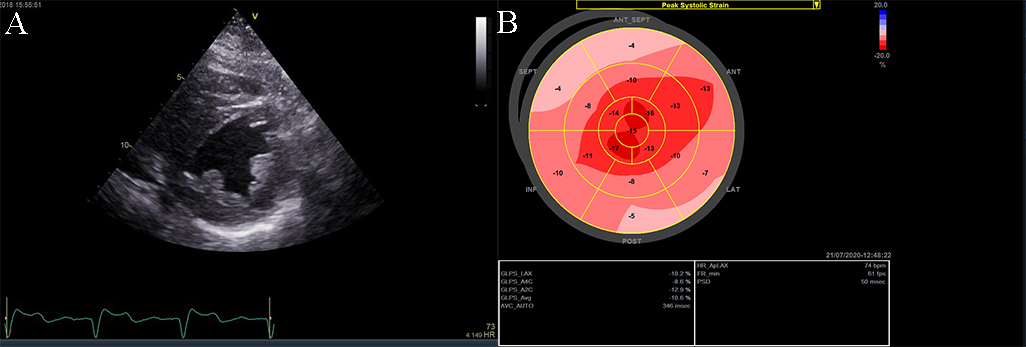

The causes of RCM can be classified as non-infiltrative (familial) or infiltrative (storage diseases), but the same pattern can be found in other disorders like diabetic cardiomyopathy, scleroderma, and endomyocardial fibrosis [38, 39, 40]. An accurate myocardial investigation by MRI and myocardial scintigraphy allows the diagnosis of different types of myocardial amyloidosis which is increasingly observed in the elderly either by transthyretin (aTTR) or by AL–light immunoglobulin chains in different plasmacytomas [41]. Another type of RCM is found in sarcoidosis and it can cause global or regional LV wall motion abnormalities. In some cases, the changes are specifically revealed on the basal posterior and lateral wall of the LV [42, 43, 44]. The most common finding is myocardial thinning, but RCM can also present with hypertrophy or it can include myocardial aneurysms [38, 45, 46, 47]. In some RCMs such as endomyocardial fibrosis or hypereosinophilic syndrome apical intraventricular thrombosis may be recognized; this may be responsible for pulmonary or systemic cardioembolism [48]. In RCM due to amyloidosis, apart from hypertrophy and wall motion abnormalities (Fig. 9), valvular involvement may also be noted with thickened aortic cusps or mitral leaflets determined by local deposition of amyloid [49].

Fig. 9.The echocardiographic aspect of cardiac amyloidosis, associated with aortic stenosis. (A) short-axis view, showing left ventricular hypertrophy. (B) Speckle tracking echocardiography obtained by measuring longitudinal strain in apical 4 chamber view, shows a significantly reduced GLS (global longitudinal strain) of –8.6%.

2D echocardiography, as mentioned before, highlights a low or normal diastolic volume of the LV associated with normal or only mildly reduced LV ejection fraction, as criteria for RCM. Also, one or both atrial enlargement is identified, with increased pressures, and normal pericardium. Once the typical pattern of RCM is identified, the echocardiogram can reveal also some features for a specific etiology. For example, in cardiac amyloidosis, the left and right ventricular walls are often mildly and symmetrically thickened, the myocardium may have a granular appearance, and myocardial strain imaging may show preserved apical function. However, it is not sufficient information neither to confirm, nor exclude cardiac amyloidosis [39, 40, 50], and further testing is needed. Moreover, in sarcoidosis global or regional (typically basal posterior and lateral) LV wall motion abnormalities may be observed. The most common finding is myocardial thinning, while less common findings include myocardial aneurysms, hypertrophy, and pericardial effusion [51, 52]. In eosinophilic inflammation of the myocardium or hypereosinophilic syndrome, the echocardiogram is often unrevealing during the initial necrotic stage. In the thrombotic stage of the disease, the damaged endocardium may have associated thrombus, predominantly involving the ventricular apex [3, 5, 38, 52, 53]. During the last, fibrotic stage, increased endomyocardial echogenicity is seen, affecting one or both ventricles, sometimes with overlying thrombus; the ventricular filling can be restricted, and atrioventricular valve leaflets may be tethered [53, 54, 55]. A pattern similar to hypereosinophilic syndrome can emerge in endomyocardial fibrosis. It may be characterized by LV, RV, or biventricular apical fibrosis [53, 54, 55]. In radiation-induced RCM the echocardiogram may show structural abnormalities within the field of radiation, such as calcified heart valves, a thickened pericardium, or focal wall motion abnormalities related or not to radiation-associated coronary artery disease [40, 42, 56, 57].